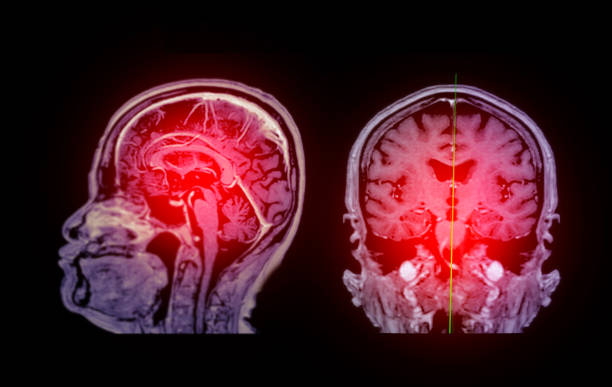

腦缺血缺氧引起的缺血性腦卒中是一種致殘率較高的腦血管疾病。缺血性中風是全世界殘疾和死亡的主要原因。據報道,缺血性腦卒中30天內的死亡率為5%~15%,致殘率可能超過50%。超過40%的幸存者再次經歷缺血性中風,死亡率和致殘率更高。